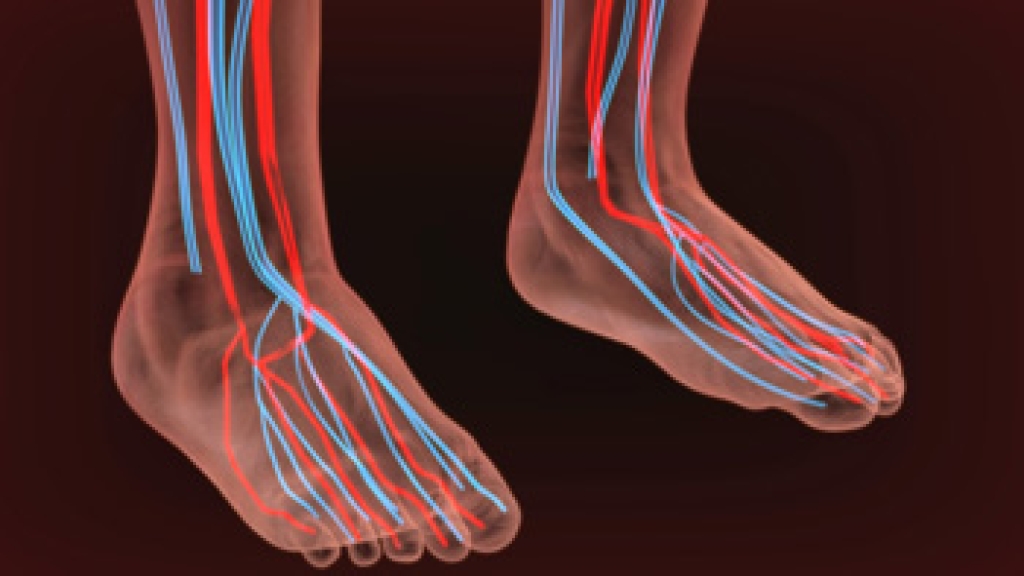

- Loss of circulation in legs & feet

Diabetes and poor circulation can cause general loss of sensitivity over the years, turning a simple cut into a serious issue.